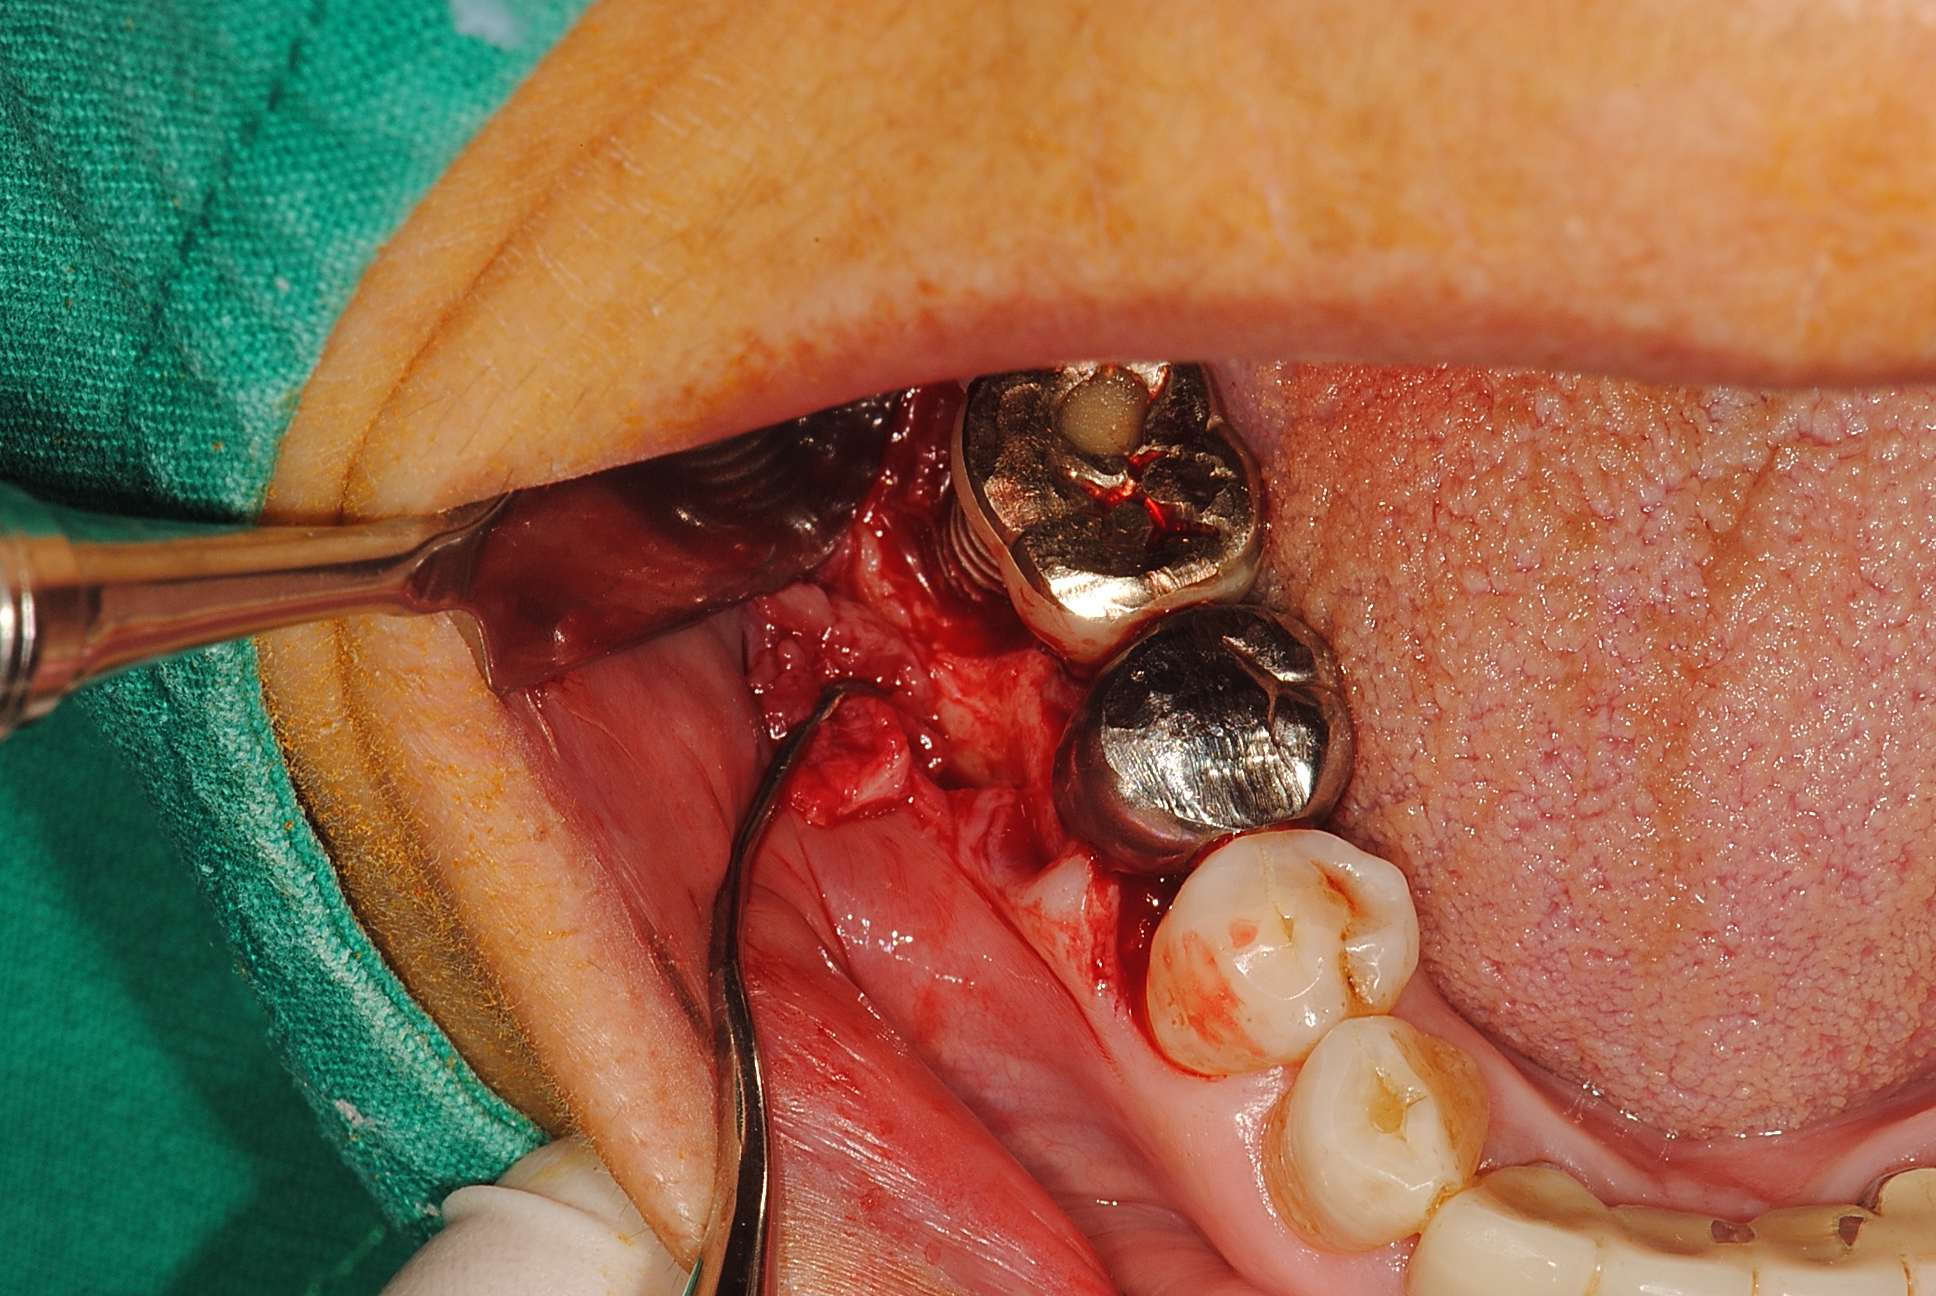

사진에서 보이듯

임플란트주위염부위를 절개를 하면 뼈가 흡수되있는 것을 볼수 있습니다.

물리적으로 임플란트 픽스처의 thread의 제거하였으며

화학적으로 해독과정을 진행한 케이스입니다.